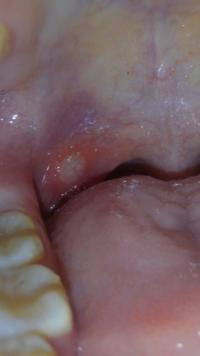

扁桃腺の近くに口内炎みたいなものがあります 唾を飲み込む時など少し Yahoo 知恵袋